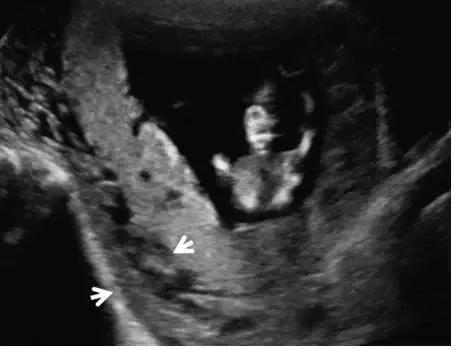

副胎盘

副胎盘是指一个或多个附属胎盘小叶通过血管与主胎盘相连,其发生率在所有妊娠中约占 5%~6%,在高龄孕妇及人工授精时发生率还会高一些。双胎盘是副胎盘的一个变异,其两叶胎盘的大小近似(图 4)。 在超声上,副胎盘表现为两个独立的胎盘通过脐带与主胎盘相连(图 5)

图 5 A 示孕 26 周的胎盘横切面,箭头示 2 个独立的胎盘小叶(长箭头),箭号指示二者之间可见脐带起源于此;图 B 为孕 34 周胎儿死亡后的胎盘大体病理标本,箭头示两个独立的胎盘由源自主胎盘的脐带相连接;该胎儿的死因是由于较大脐膨出导致脐带扭结、脐血管破裂

副胎盘应与一个胎盘附着于宫腔的两个部位相区别。需注意,子宫收缩可形似副胎盘,复查超声即可将二者区别开来。胎儿娩出后,副胎盘可因未被发现而滞留宫腔引起产后出血。副胎盘容易并发血管前置及帆状胎盘。